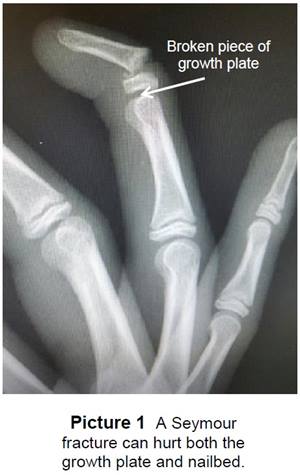

A Seymour (see-more) fracture is a break in the bone at the end of the finger or toe at the first

joint (Picture 1). It often happens when a finger

or toe is crushed or bent back too far.

In children, there is a growth plate at the end of

their bones. It is the weakest part of the bone

until the bone stops growing. Where a nail starts

to grow (nailbed) is located near the growth plate.